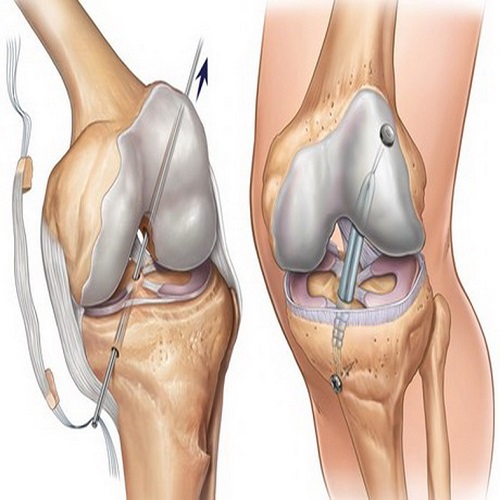

Artroskopik Menisküs Onarımı Nedir? Artroskopik menisküs onarımı, diz eklemindeki menisküs adı verilen kıkırdak dokusunun, minimal invaziv bir cerrahi prosedür olan artroskopi yöntemiyle onarılması işlemidir. Menisküs, diz eklemleri içinde bulunan C şekilli kıkırdak yapıdır ve ek yüzeylerin düzenli bir şekilde yük görünümünü sağlar. Ancak travma, aşırı zorlanma veya yaşlanmaya bağlı olarak menisküs yırtılabilir. Artroskopik menisküs onarımı,…